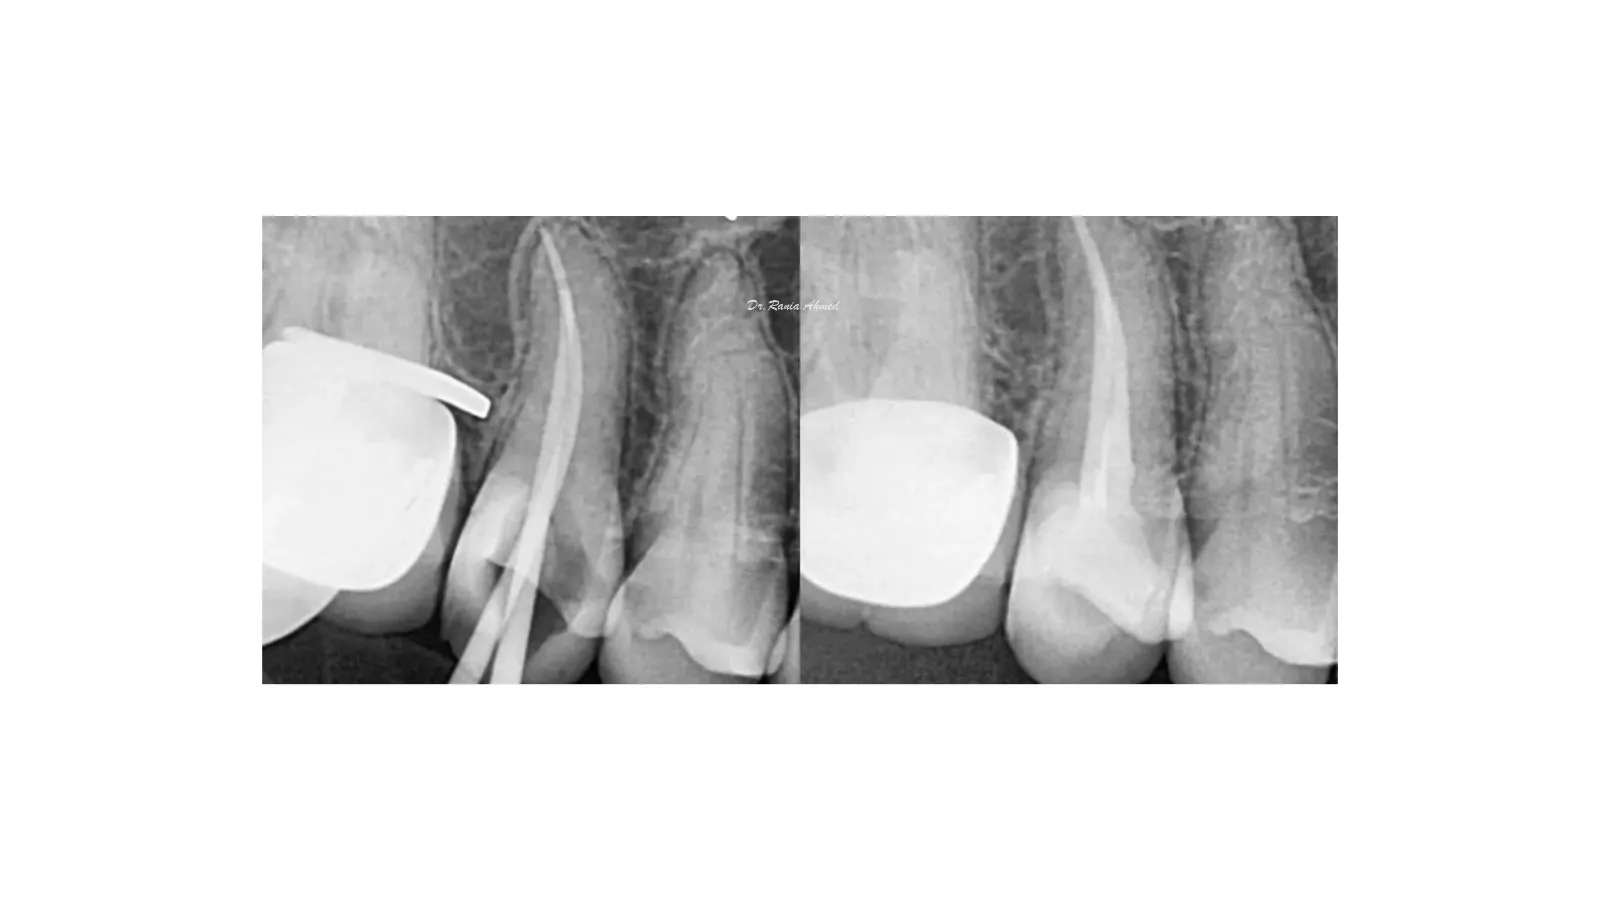

Endodontic Treatment